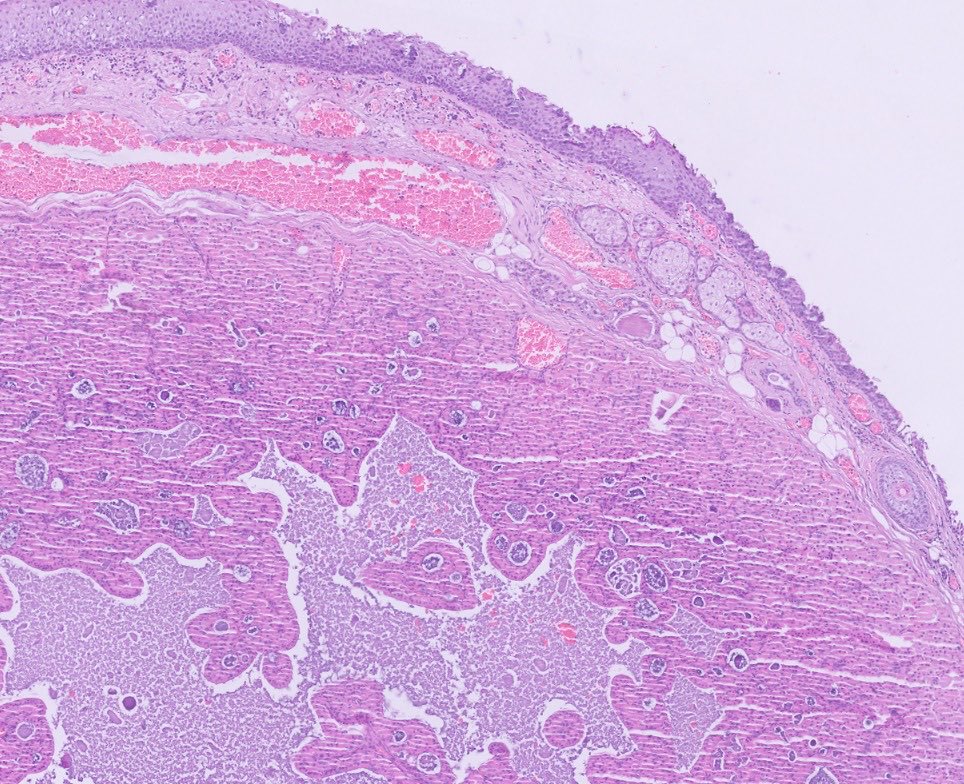

A 35 Yr | 👨 "Cyst Chronicles: Secrets of the premolar prison" ● Right Mandible 🎯 Shoot your 2 most favored DDx's @Pathologists #PathTwitter #pathX #pathresidents #HeadandNeckPath